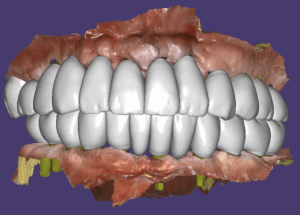

위에는 11개, 아래는10개의 임플란트를 발치와 동시에 즉시 식립했으며 위에는모두, 아래는 8개의 임플란트에 지대주를 연결해서 임시치아를 제작해 세팅했습니다.

수술 후 4개월에 최종보철을 만들기 위한 스캔바디 스캔을 한 후 최종보철을 만들어 끼웠습니다. 즉시하중 임시치아를 적용했지만 모든 임플란트는 골융합이 잘 되었습니다.

치료전 환자의 구강위생이 불량해서 28개의 치아로 만들지 않고 전체 24개의 치아로 마무리를 했어요. 일반적으로 제일 마지막 어금니가 너무 뒤쪽까지 있을 때 위생관리를 잘 못하시는 분들이 관리가 잘 안되기 때문입니다.